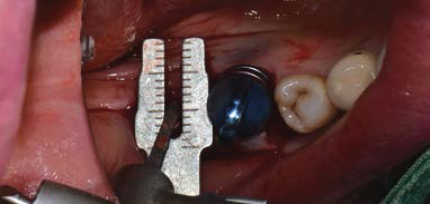

Volume Up Gauge를 Implant 식립부위에 위치하여 Healing Abutment 직경 확인

Volume Up Gauge의 홈에 맞춰 Point Drill의 위치 파악

Volume Up Gauge로 직경 확인 (Ø8.5)

-

Volume Up Gauge홈에 맞춰 Point Drill 위치